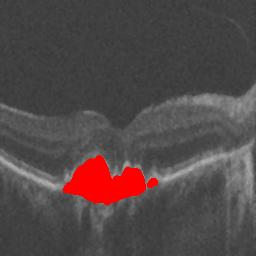

The qualitative results of the proposed system is shown in the Fig. 3. The detection task is evaluated using Area Under the Curve(AUC) metric and the segmentation task is evaluated using Dice Coefficient(DC) metric and the results are presented in Table1

| (a) De-noised OCT slice | (b)Predicted fluid region | (c)Manual fluid segmentation |

| (d) De-noised OCT slice | (e)Predicted fluid region | (f)Manual fluid segmentation |

| (g) De-noised OCT slice | (h)Predicted fluid region | (i)Manual fluid segmentation |

| (j) De-noised OCT slice | (k)Predicted fluid region | (l)Manual fluid segmentation |

| (m) De-noised OCT slice | (n)Predicted fluid region | (o)Manual fluid segmentation |